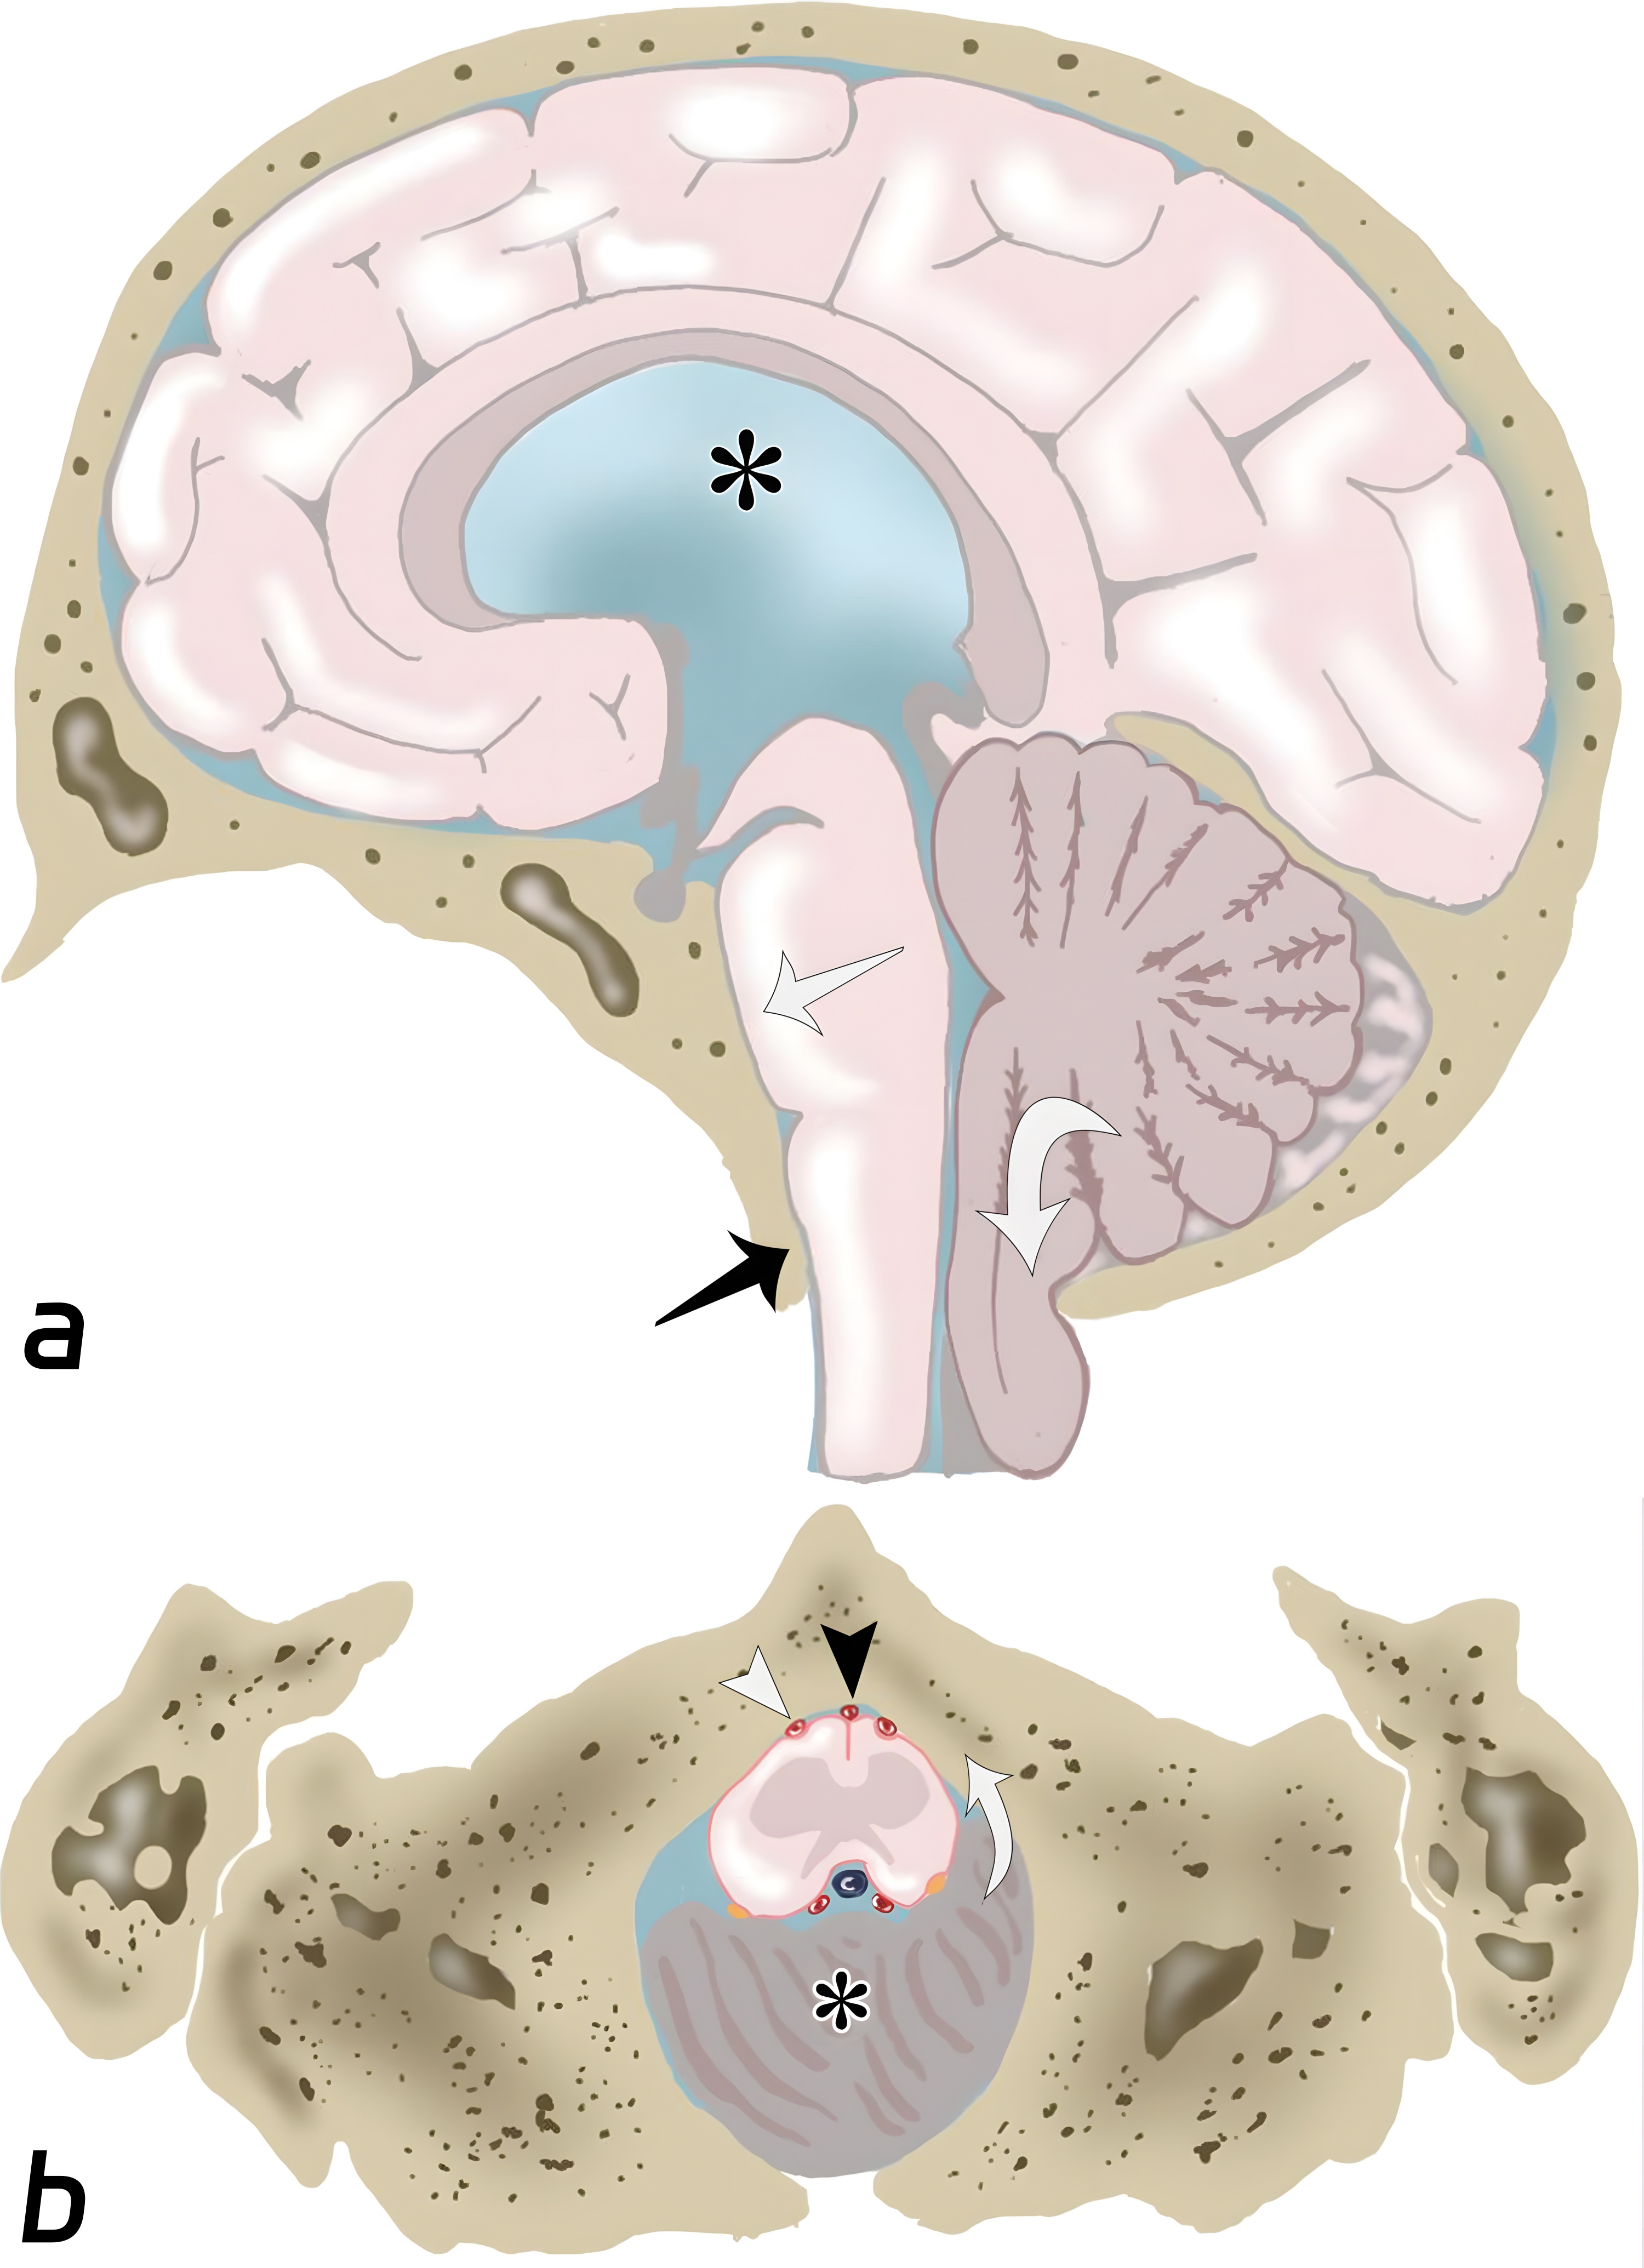

小脑扁桃体疝的示意图。(a图)小脑扁桃体延伸至枕骨大孔的下方(白色弯曲箭头),脑干挤压斜坡(白色长箭头),延髓池的闭塞(黑色长箭头),梗阻性脑积水(黑色*)。(b图)枕骨大孔层面的轴位图,移位的小脑扁桃体(黑色*)导致周围脑脊液的闭塞,延髓向前移位(白色弯曲箭头),挤压脊髓动脉(黑色短箭头)及椎体动脉(白色短箭头)。